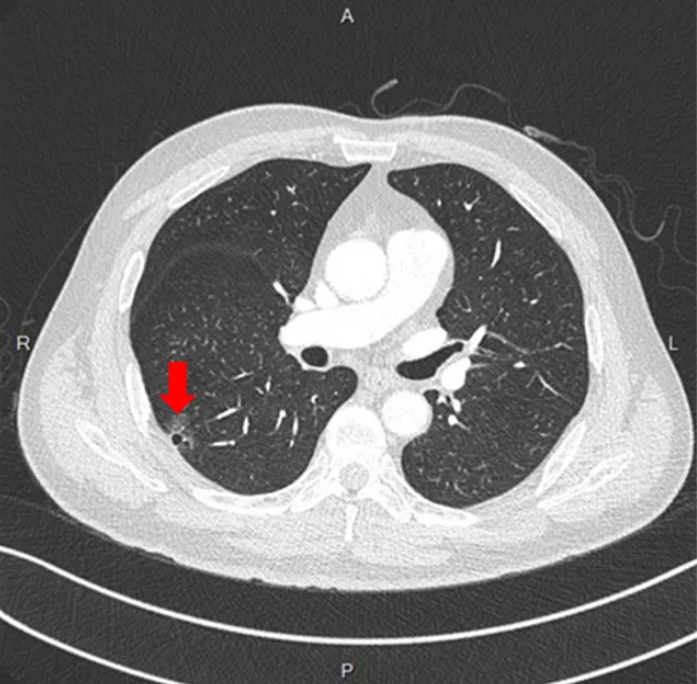

今年4月,赵先生来到北京燕化医院胸心外科门诊就医要求住院。马振东主任详细询问得知,患者在2月前因胸痛在北医三院查胸部CT,发现右肺中叶3×2.5cm毛玻璃结节,医生给予抗炎药物治疗。前几天再次复查胸部CT发现结节无明显变化,医生建议入院系统诊治。赵先生全家经过商量后决定到我院治疗,于是马主任将其收入院治疗。

患者入院后完善了相关的化验及检查,虽然肺癌监测结果未见异常,但李简教授和马振东主任通过仔细阅读胸部增强CT片及综合分析病情,考虑患者肺部结节恶性可能性极大。于是在与患者一家充分沟通病情后,为患者进行了右肺下叶背段切除手术。术后病理回报:右肺下叶附壁型肺腺癌。患者病变局限,无远处转移,目前恢复很好,对胸心外科团队诊疗水平和服务十分满意。